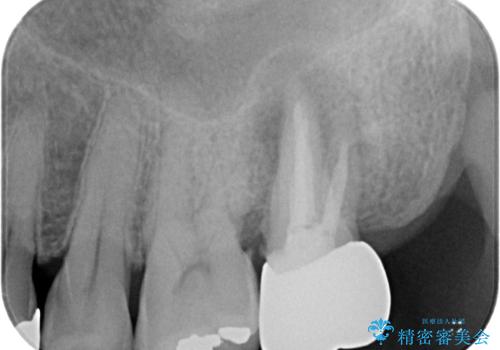

レントゲンや診察を行ったところ、抜歯となる可能性はありましたが、まずは銀歯を外した上で根管治療を行うことが可能であるか判断することが先決であるとご説明し、根管治療とインプラント治療の双方をご案内し、治療を開始することとしました。

骨の透過像が非常に大きく、根管も大きく削られていたため、歯根破折による抜歯の可能性がありましたが、根管治療可能な状態でした。

初回治療後には速やかに痛みが改善され、非常に大きかったレントゲンでの骨透過像も改善されました。